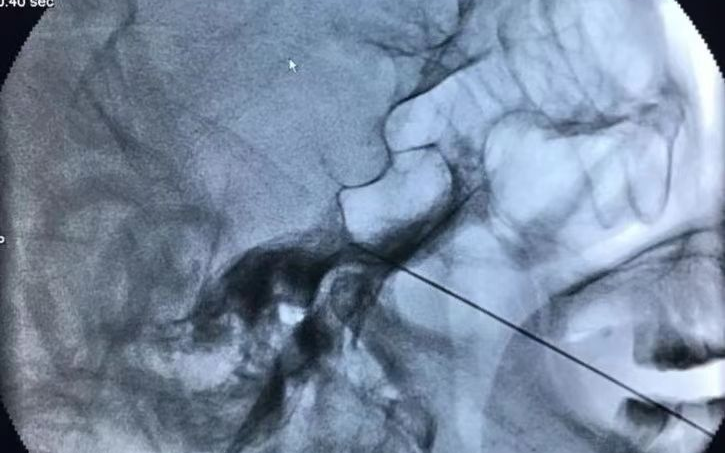

射频神经毁损术干预三叉神经痛,是在X射线和CT引导下将射频针经皮刺入三叉神经节处,选择性破坏传导痛觉、温觉神经,达到止疼效果,适用于年老体衰有系统疾病,不能耐受手术者。

☑ 定位准确:在C型臂或CT下精准定位,射频针直接作用在病变神经上,数据精确到1毫米以下,角度误差小于1度,且仅对病变神经进行处理。